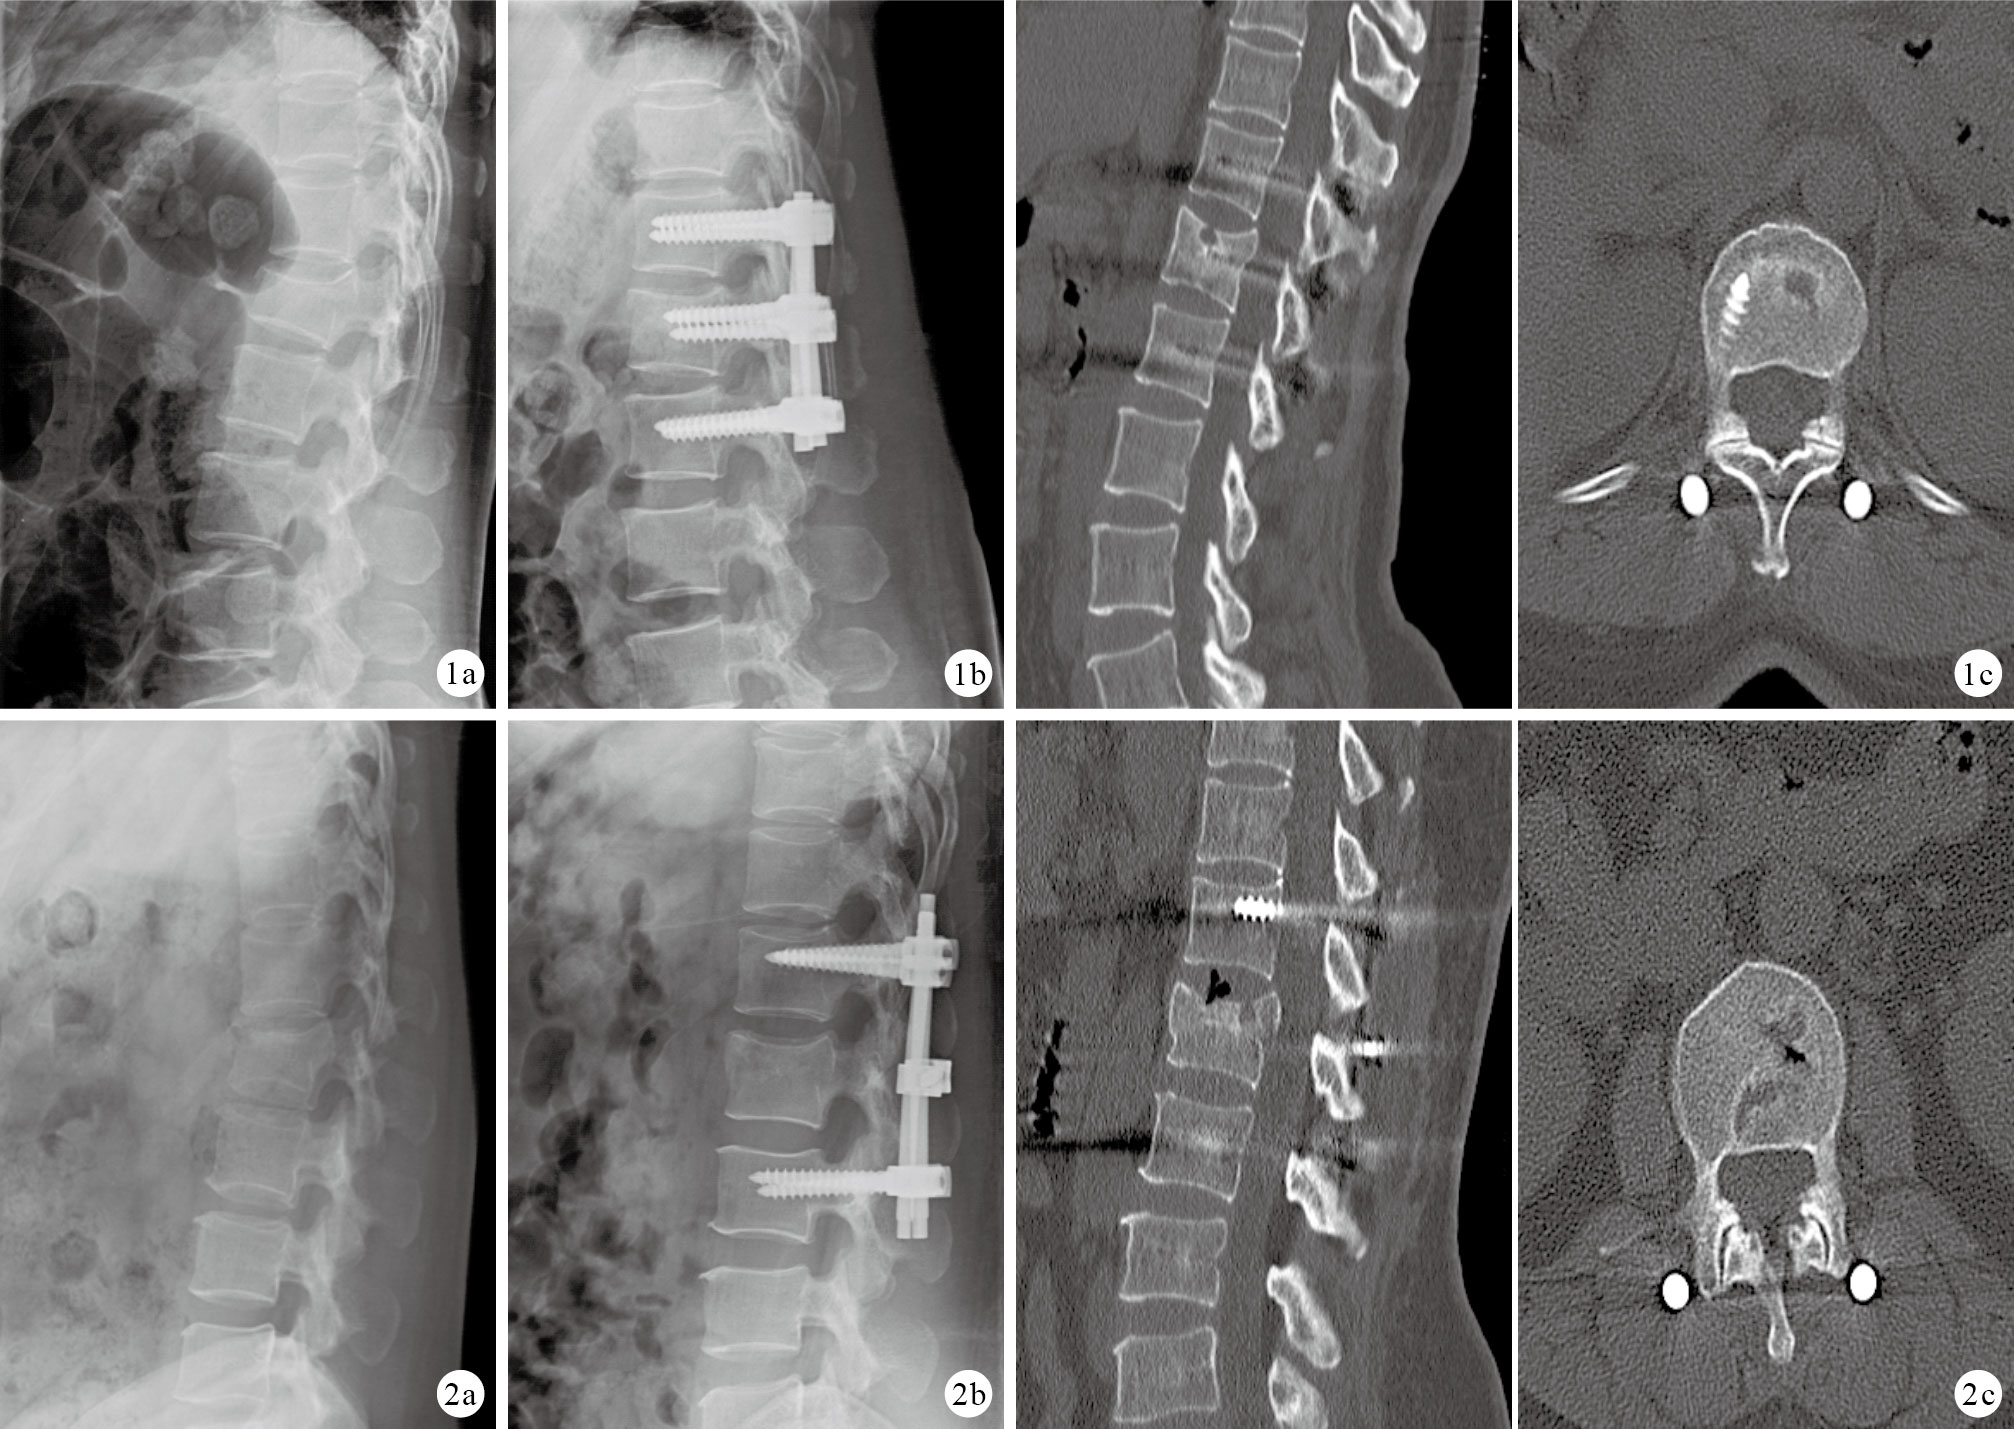

A、B組患者手術時間分別為(127.3 ± 33.4)、(130.2 ± 33.2)min,術中出血量分別為(327.6 ± 92.7)、(325.5 ± 87.9)mL,比較差異均無統計學意義(t=0.258,P=0.800;t=0.127,P=0.901)。患者切口均Ⅰ期愈合,無感染及下肢深靜脈血栓形成等早期并發癥發生。40例均獲隨訪,隨訪時間12~16個月,平均14.8個月。X線片復查示,兩組植骨均獲骨性融合,A、B組融合時間分別為(7.42 ± 0.62)、(7.71 ± 0.45)個月,比較差異無統計學意義(t=0.341,P=0.856)。隨訪期間均無內固定物斷裂、松動等并發癥發生。見圖 1、2。術后兩組均行內固定物取出,A組為術后11~14個月,平均12.4個月;B組為術后11~15個月,平均12.9個月。術后12個月A、B組神經功能Frankel分級改善評分分別為(0.52 ± 0.72)、(0.47 ± 0.63)分,比較差異無統計學意義(t=0.188,P=0.853)。